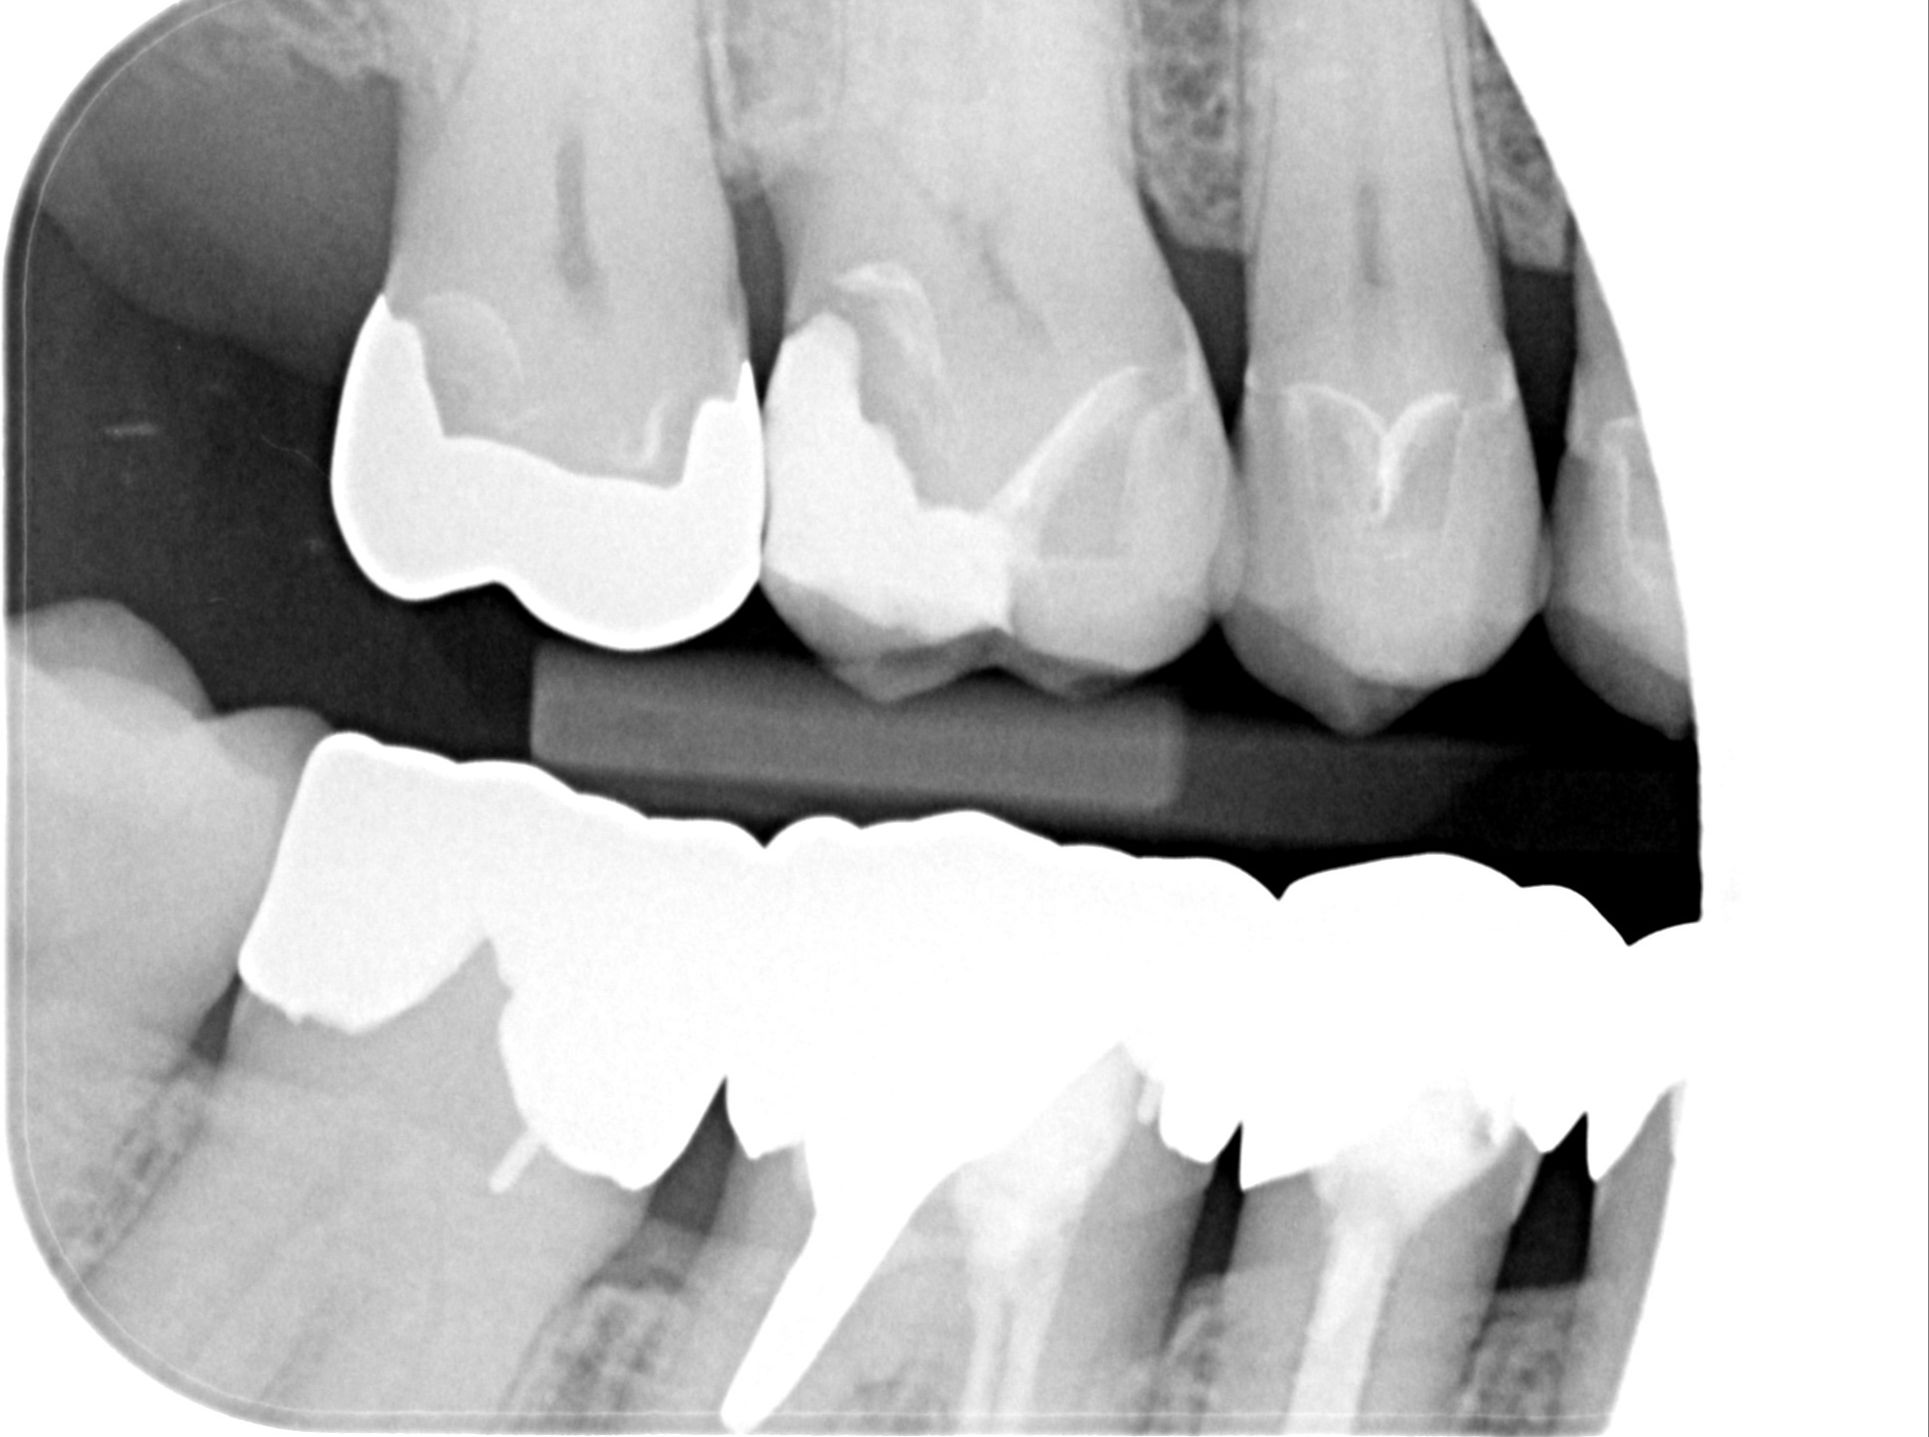

Teilkronen und ein Inlay

Ich bin Herrn Dr. xxx sehr dankbar. Er hat sich meine Zähne angeschaut und die mitgebrachten Röntgenbilder. Er war total begeistert von meinen alten Kronen und hat mir versichert, dass daran überhaupt nichts gemacht werden muss. Unfassbar, dass mir ein anderer Zahnarzt alles erneuern wollte.